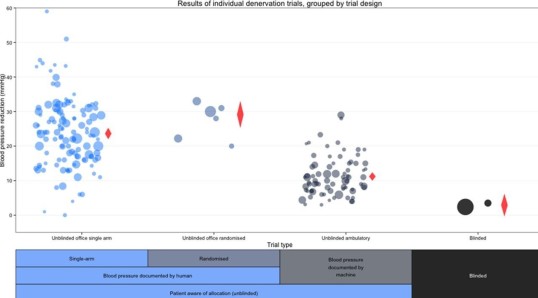

- Influence of bias in renal denervation trial, a meta-regression - Heart & Circ. Cardiovasc. Qual. Outcomes

- Renal denervation - Cardiovasc. Revasc. Med.